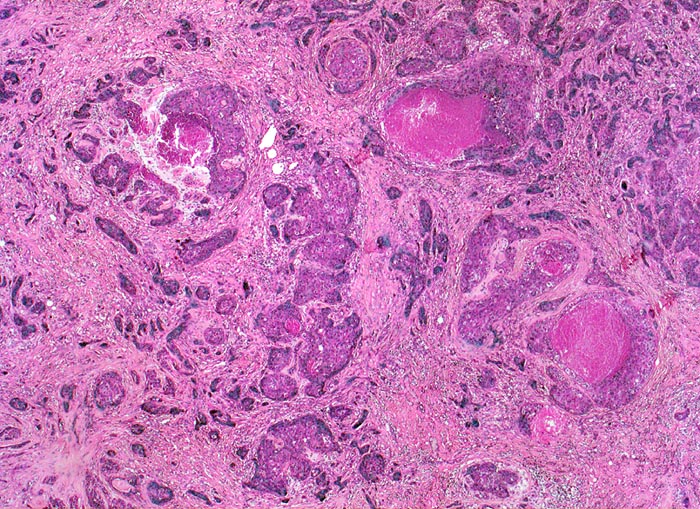

PathoPic – image database / PathoPic ID 4664 - wenig differenziertes invasives duktales Mammakarzinom

wenig differenziertes invasives duktales Mammakarzinom

Das Karzinom bildet keine drüsigen Strukturen, sondern ausschliesslich solide Zellstränge mit infiltrativem Wachstum in desmoplastischem Stroma. Fokal sind Tumornekrosen erkennbar.

Makroskopisch: derber weisser Herd von 2.2cm Durchmesser im oberen äusseren Quadranten.

Der vorliegende Tumor hat einen hohen Anteil solider Tumorareale, zeigt ausgeprägte Zellatypien und zahlreiche Mitosen entsprechend einem wenig differenzierten Karzinom.